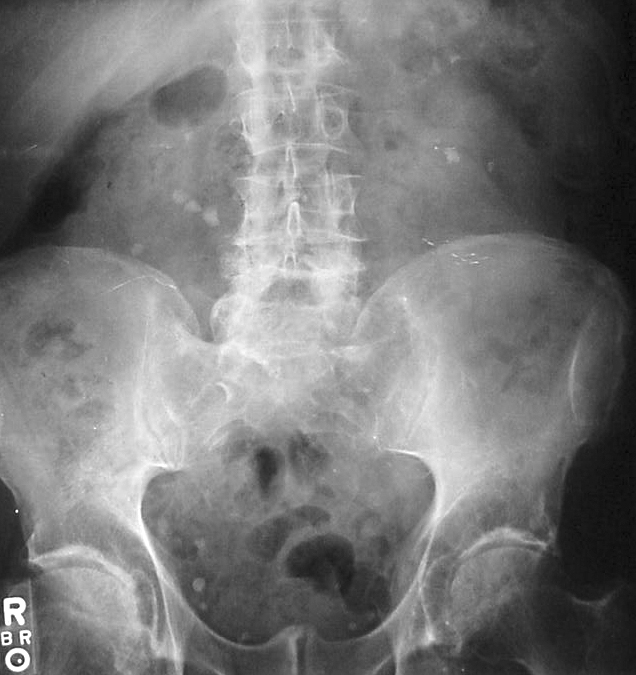

This three-arm RCT of 1,645 renal colic patients in Qatar found that IM diclofenac was slightly more effective than IV morphine or IV paracetamol, with fewer adverse effects. The utility of the study is limited by use of drugs not available in North America, and the lack of an NSAID + opioid treatment arm; while not currently practice-changing for us, this article generates critical thought on the use of opioids during a time where narcotic abuse is increasingly problematic.